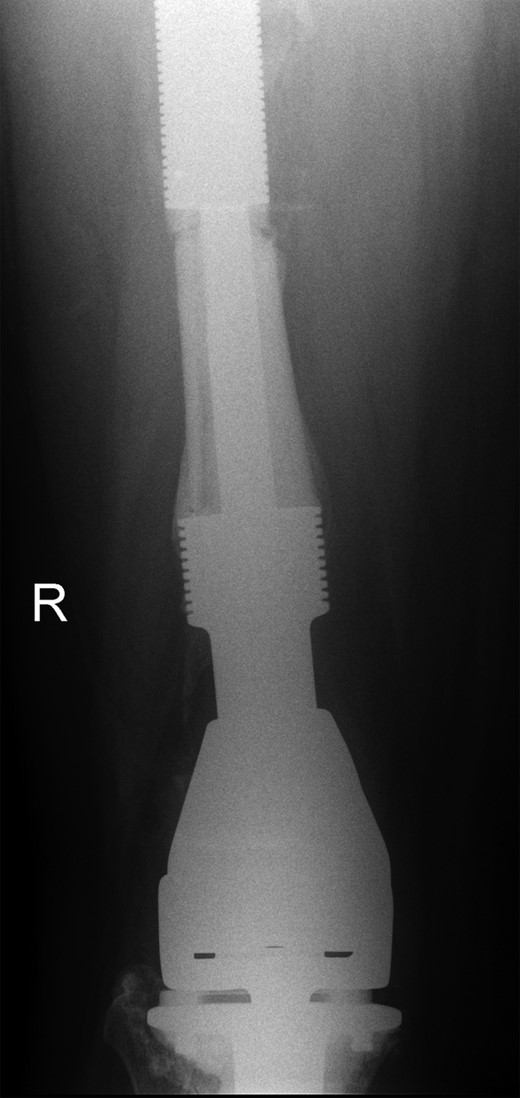

Custom-made cement-linked internal proximal femoral replacement.

Existing distal femoral replacement with stem linked to custom-made internal proximal femoral component visible in upper half of the image.